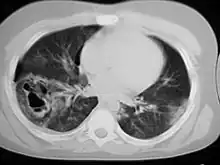

A chest CT scan revealing pulmonary contusions, pneumothorax, and pseudocysts

Computed tomography (CT scanning) is a more sensitive test for pulmonary contusion,[6][33] and it can identify abdominal, chest, or other injuries that accompany the contusion.[38] In one study, chest X-ray detected pulmonary contusions in 16.3% of people with serious blunt trauma, while CT detected them in 31.2% of the same people.[45] Unlike X-ray, CT scanning can detect the contusion almost immediately after the injury.[43] However, in both X-ray and CT a contusion may become more visible over the first 24–48 hours after trauma as bleeding and edema into lung tissues progress.[46] CT scanning also helps determine the size of a contusion, which is useful in determining whether a patient needs mechanical ventilation; a larger volume of contused lung on CT scan is associated with an increased likelihood that ventilation will be needed.[43] CT scans also help differentiate between contusion and pulmonary hematoma, which may be difficult to tell apart otherwise.[47] However, pulmonary contusions that are visible on CT but not chest X-ray are usually not severe enough to affect outcome or treatment.[37]